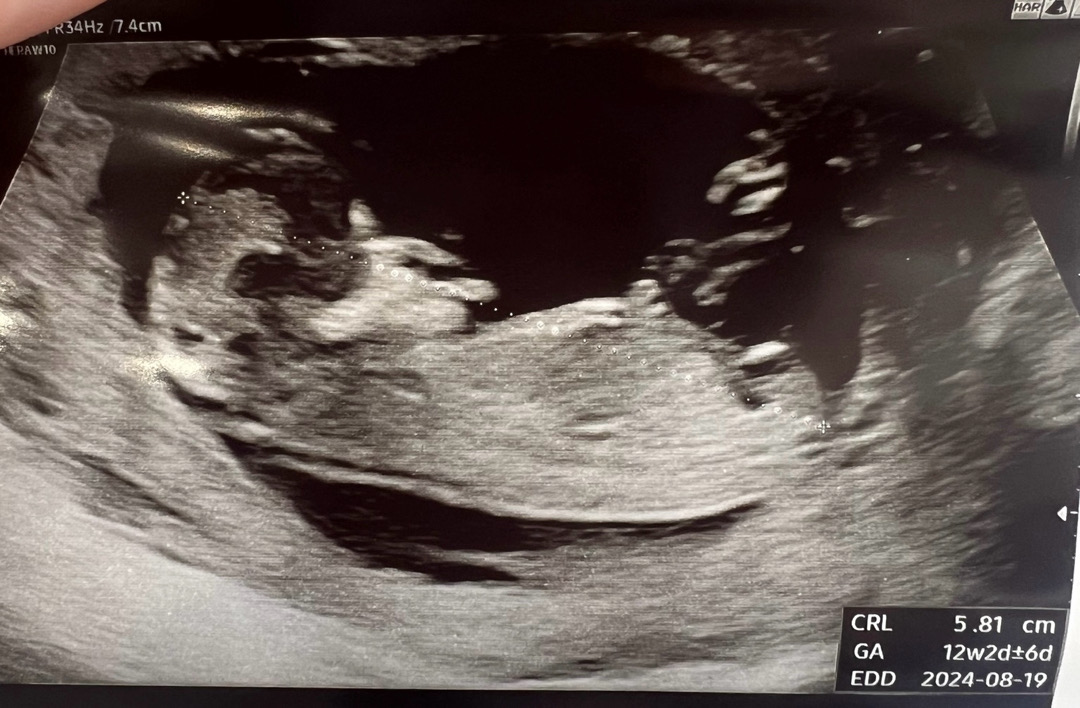

12주 초음파 성별 어떻게 보이시나요??

어떻게 보이시나요!?